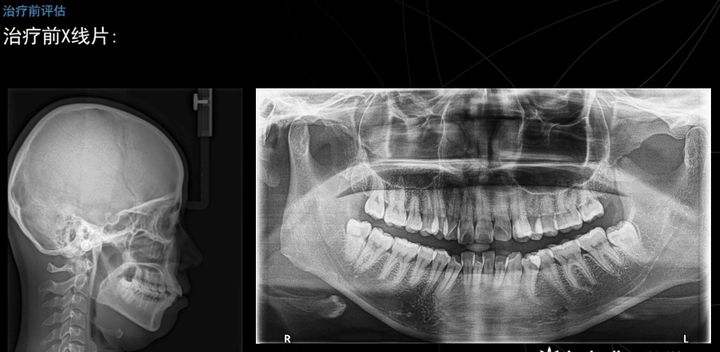

下图是他的头颅定位测位片和全颌曲面断层片,可以看到髁突的一个大概形态以及头颅,侧帽,软组织,牙齿的一个关系。

这是我们进行一个头影测量的描记,几个简单数据的记录,她的ANB角是4.8度,轻度的骨性二类的患者,她的下颌平面角是33度,是均角型的,她的下颌形态也比较好,基本接近偏平长方形。

头影测量的数据,比较异常的就是这个ANB角,我们诊断她是属于一个安氏一类,骨性二类,深覆合深覆盖牙列拥挤,上下颌骨存在一个失状向不调。我们觉得她失状向不调,可能上颌前突的程度要占据更多的一个因素。

可以看到她矫正后的头颅定位测位片和全额曲面断层片,侧貌可以看到她的突度已经明显的改善了许多,髁肌紧张也大大缓解了不少,可以看到治疗前ANB为4.5,治疗后变成3.8,下颌平面角也由33度变成32.5度,上颌前牙的角度也相应改变,虽然变化的度数不是特别大,但是能看到她的外貌上面是柔和了很多,突度也有了明显的改善。